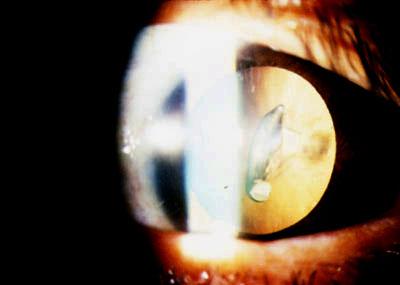

诊断:眼内异物(钉子)

病史:一28岁的男建筑工人因高速飞行的金属碎片刺入眼睛而来急诊。

临床特征:裂隙灯检查出钉子上的金属碎片穿透巩膜并悬浮在玻璃体腔。钉子附着在视网膜外层。